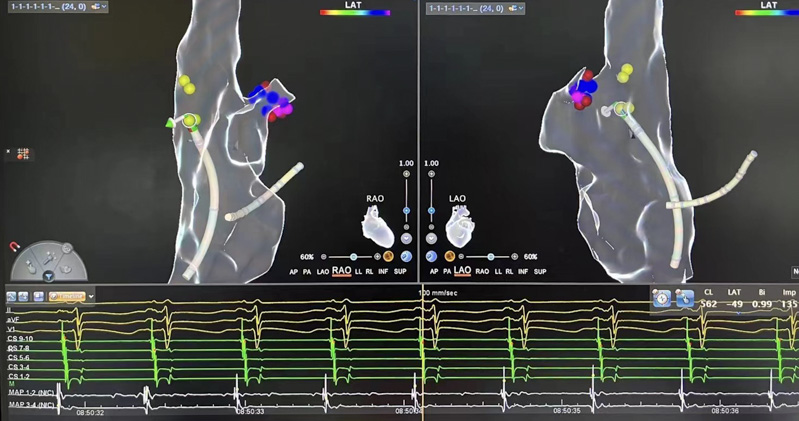

▲術中測標

介入室內,心血管內科電生理團隊開始為患者進行心電生理檢查,在三維系統指引下行激動標測提示心律失常起源于右心耳根部。右心耳是右心房的盲端,非常菲薄,大約只有1-2mm,附近有竇房結、上腔靜脈等重要結構,在此處消融,有心臟穿孔、損傷竇房結導致心臟停搏等風險。

劉艷麗主任綜合評估后,憑借著高超的技巧,果斷為患者進行射頻消融,最終患者心動過速中止,即刻恢復竇性心律。